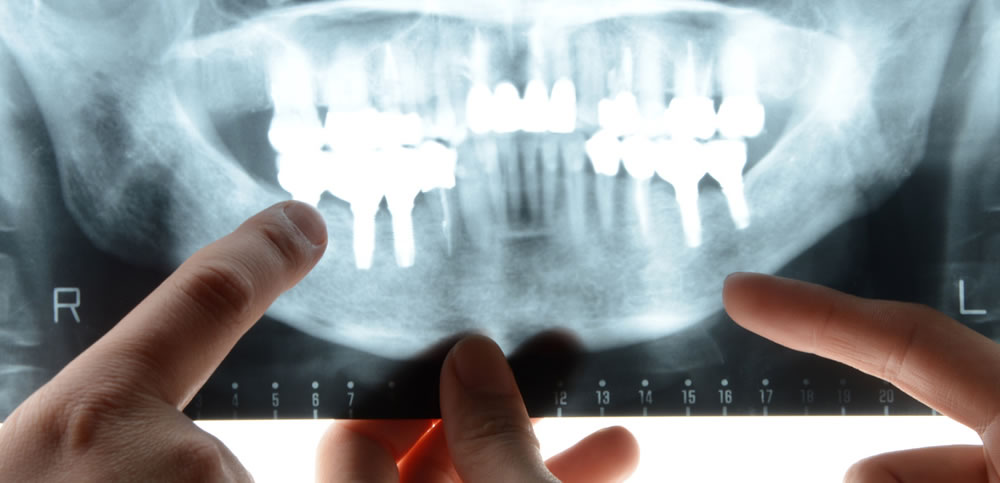

CT精密検査・事前シミュレーションの徹底

インプラント治療では、事前にCTによる精密検査を行い、顎骨の高さ・厚み・密度をはじめ、周囲の血管や神経、上顎洞の位置などを3次元画像で詳細に確認します。

得られたデータをもとに、埋入位置・角度・深さを事前にシミュレーションし、リスクを十分に考慮したうえで適切な治療計画を立案いたします。